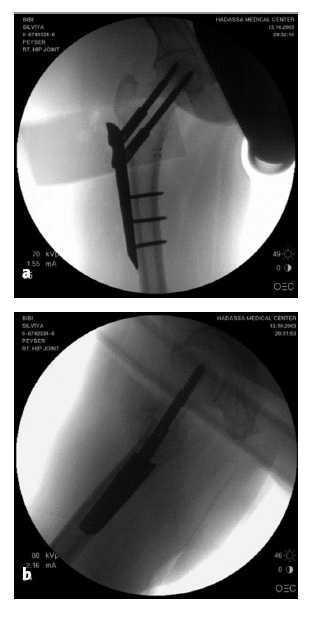

Figura 14

La placa PCCP™ se encuentra colocada en su lugar tanto en el plano AP (a) como en el lateral (b).

El introductor (nº 7) se retira aflojando el tornillo en mariposa (nº 8).

La herida se irriga y se cierra colocando un drenaje espirativo. Cierre cutáneo con grapas.